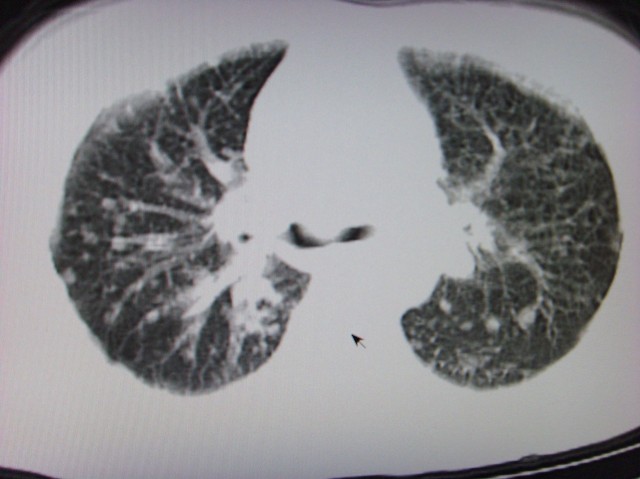

标题: CT7125:中央性肺Ca.

典型 中央型ca伴双肺、淋巴结转移

还有肺不张

典型 中央型ca伴双肺、淋巴结、胸膜转移

中心型肺癌伴双肺转移及纵隔淋巴结转移,癌性淋巴管炎

首先考虑中央型肺癌伴阻塞性肺炎双肺、淋巴结转移,可以正规抗炎治疗一周后复查